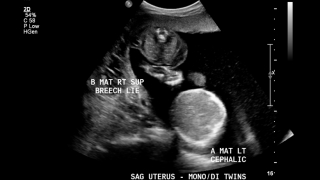

5.) Twin-to-Twin Transfusion Syndrome

TTTS is a syndrome that can occur in monochorionic-diamniotic twins (each baby has its own sac, but they share the placenta), in which one baby takes blood from the other.

TTTS can be detected and diagnosed through ultrasound. Several indications are used in diagnosing this syndrome, differing between the donor (baby giving blood) and the receipient (baby receiving extra blood).

In the donor baby, symptoms include oligohydramnios (too little/no fluid around baby), little/no urine in the bladder, and small size.

In the receipient baby, symptoms include polyhydramnios (too much fluid around baby), increased amount of urine in the bladder, and large size.

If TTTS is expected, the blood flow in the umbilical cord and brain also can be measured. These measurements can determine if the exchanging of blood is unbalanced, leading to TTTS.